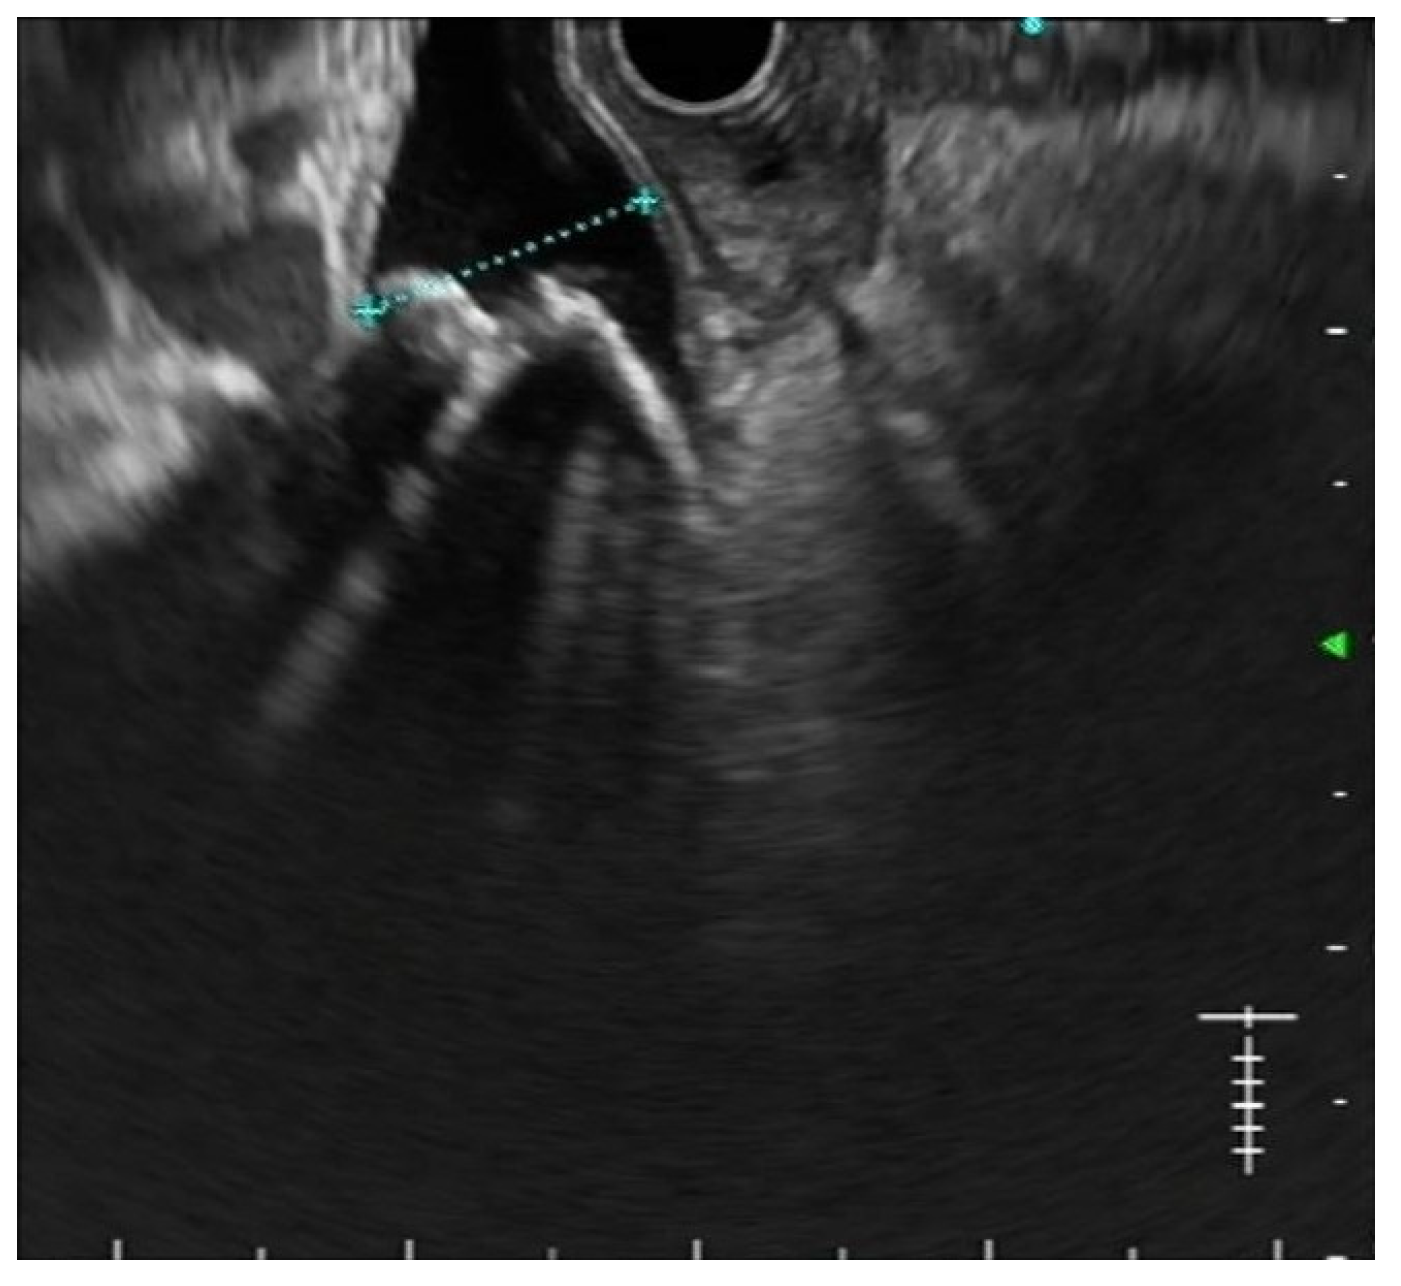

Secondly, the excellent diagnostic accuracy of EUS for CBD stones, together with its findings regarding stone number and size, is often useful in planning the best treatment strategy [20] Figure 1. In particular, performing EUS before ERCP allows predicting the expected grade of complexity of the ERCP procedure [21]. As a result, physicians may plan in advance the execution of ancillary techniques such as large balloon dilation, electrohydraulic or laser lithotripsy, cholangioscopy, and even referral to other institutions in order to improve the success rates while keeping the adverse events as low as possible [22].

Figure 1.

EUS shows multiple stones in a dilated common bile duct.